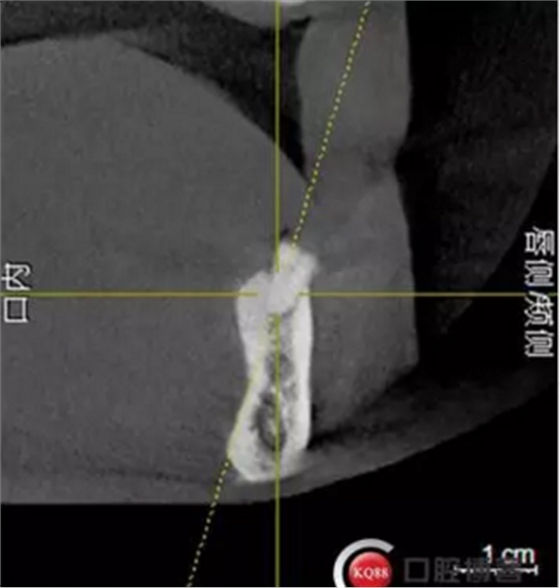

檢查:上頜無牙頜假牙穩(wěn)定性尚可,下頜3435364243殘根;33殘冠1-2度松動,其他牙齒缺失;CBCT檢查:下頜牙槽骨前牙區(qū)骨高度足,后牙區(qū)骨高度最低為8mm,骨寬度足。

2)術前準備及手術過程,測量血壓及血糖,簽種植知情同意書;嚴格遵循無菌操作,局麻下采用微創(chuàng)技術于323436分別植入osstem4.0X10,4.0X10,4.5X7; 434446分別植入osstem4.0X1O,4.0X10,4.5X7.初期穩(wěn)定性均達到了35N.CM以上;嚴密縫合,止血,種植體位點和方向與設計一致。